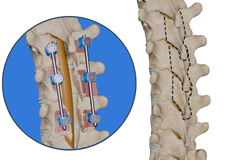

Lumbar Fusion

Spinal fusion, also called arthrodesis, is a surgical technique used to join two or more vertebrae (bones) within the spine. Lumbar fusion is the procedure of fusing the vertebrae in the lumbar portion of the spine (lower back). A piece of bone, taken from other parts of the body or donated from a bone bank is transplanted between the adjacent vertebrae. Screws, plates, or cages may be used with the bone graft to help hold the spine.

Lumbar Interbody Fusion

Lumbar interbody fusion (LIF) surgery is a surgical technique that involves the removal of a damaged intervertebral disc and the insertion of a bone graft into the disc space created between the two adjoining vertebrae. Bone grafts promote healing and facilitate fusion. Screws and rods are used to stabilize the spine during the healing process.